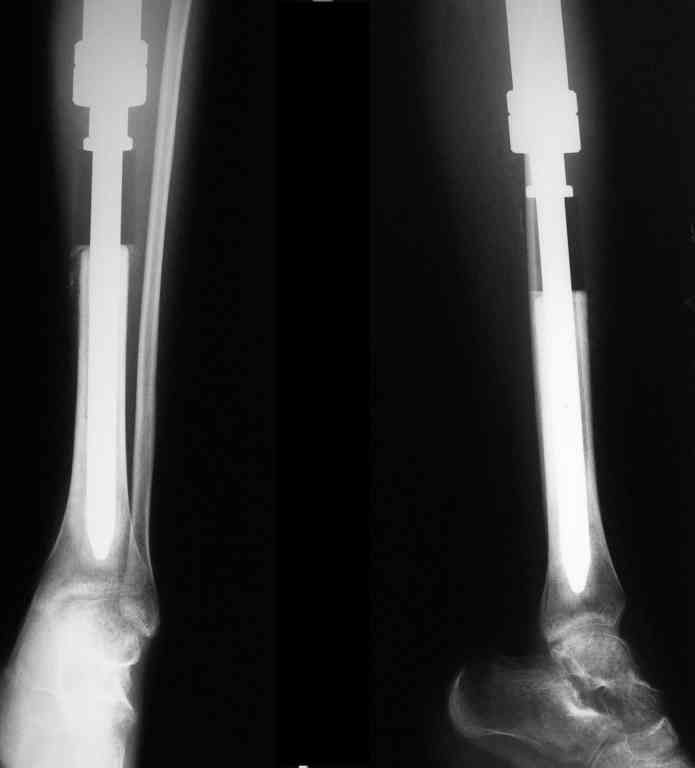

Уважаемые коллеги! Хотелось бы узнать ваше мнение о тактике лечения пациентки 16 лет, диагноз - б-нь Гоше I типа, состояние после резекции проксимальных 2/3 левой большеберцовой кости, тотального эндопротезирования ЛКС онкологическим эндопротезом, перипротезная инфекция.

01/08/05

09/09/05

13/01/06

Протез установлен год назад, в течение 8 месяцевфункционируют свищи, сообщающиеся с компонентами эндопротеза.

Планируется оперативное лечение, которое ранее не выполнялось по причине низких показателей крови (Тц-30, Нв-50, Лц-2,5) после химиотерапии. В настоящее время показатели крови постепенно нормализуются и встаёт вопрос о тактике хирургического лечения.

Пациентку беспокоят боли в нижней трети голени при физической нагрузки.